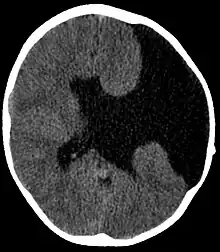

Axial CT scan showing schizencephaly in a 6-year-old child | |

Schizencephaly (from Greek skhizein 'to split', and enkephalos 'brain')[1][2] is a rare birth defect characterized by abnormal clefts lined with grey matter that form the ependyma of the cerebral ventricles to the pia mater. These clefts can occur bilaterally or unilaterally. Common clinical features of this malformation include epilepsy, motor deficits, and psychomotor retardation.[3]

Schizencephaly can be distinguished from porencephaly by the fact that in schizencephaly, the fluid-filled component is entirely lined by heterotopic grey matter, while a porencephalic cyst is lined mostly by white matter. Individuals with clefts in both hemispheres, or bilateral clefts, are often developmentally delayed and have delayed speech and language skills and corticospinal dysfunction. Individuals with smaller, unilateral clefts (clefts in one hemisphere) may be weak or paralyzed on one side of the body and may have average or near-average intelligence. Patients with schizencephaly may also have varying degrees of microcephaly, Cognitive impairment, hemiparesis (weakness or paralysis affecting one side of the body), or quadriparesis (weakness or paralysis affecting all four extremities), and may have reduced muscle tone (hypotonia). Most patients have seizures, and some may have hydrocephalus.[4]